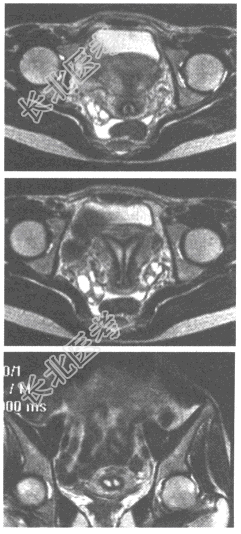

- 单项选择题患者,女性, 36岁,因不孕就诊。盆腔MRI图像如下, 最可能的诊断为

A、双角子宫

B、双子宫

C、完全性纵隔子宫

D、不完全性纵隔子宫

E、弓形子宫